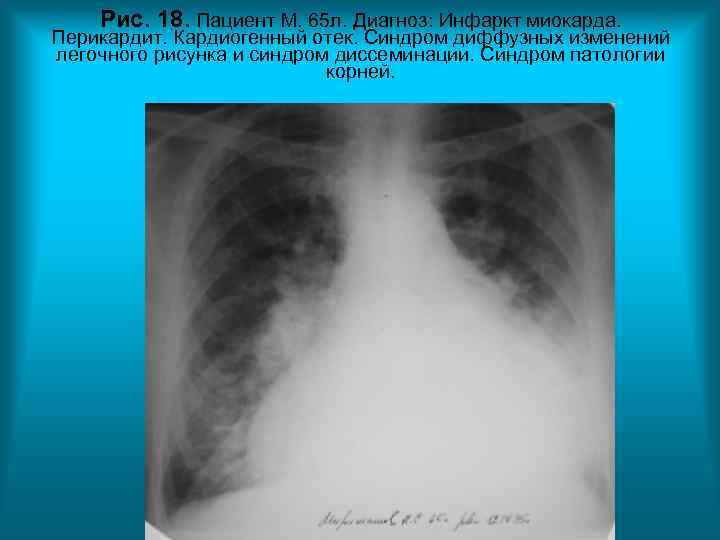

Рис. 18. Пациент М. 65 л. Диагноз: Инфаркт миокарда. Перикардит. Кардиогенный отек. Синдром диффузных изменений легочного рисунка и синдром диссеминации. Синдром патологии корней. Н. С. Воротынцева. С. С. Гольев Рентгенопульмонология